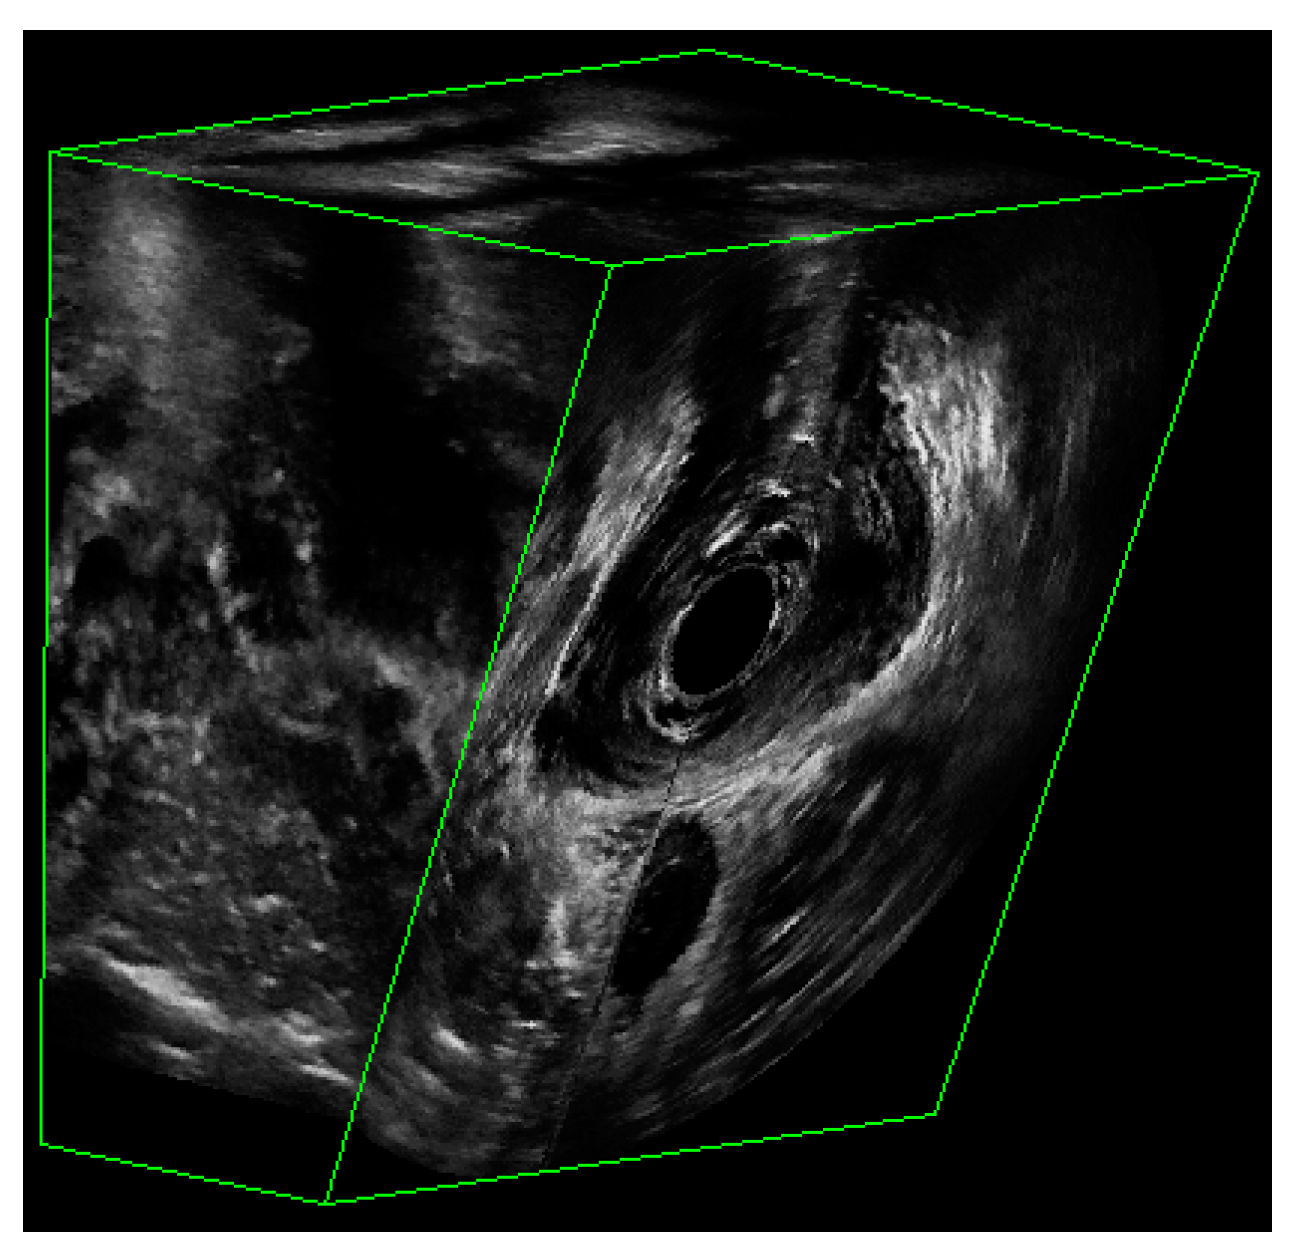

Figure 2.

The partial view of a 3D EVUS image that shows the US signal.